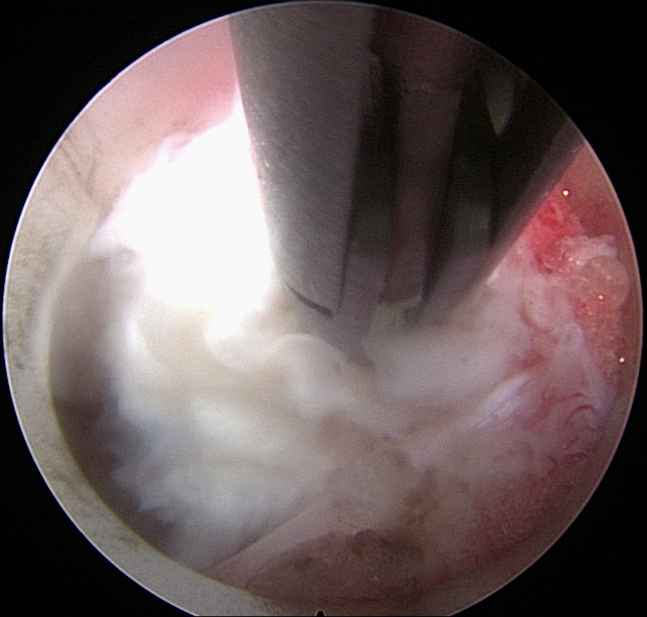

Πλάγια προσπέλαση

Πρόκειται για μια ακόμα πιο ειδική μέθοδο, κατά την οποία εισερχόμαστε μέσω του μεσοσπονδύλιου τρήματος και αποκτούμε πρόσβαση κατευθείαν στην δισκοκήλη χωρίς να χρειάζεται αφαίρεση οστικού τμήματος. Αποτελεί την λιγότερο επεμβατική μέθοδο όλων στην σπονδυλική στήλη, αφού χρησιμοποιεί φυσικά τρήματα για την είσοδο στον σπονδ. σωλήνα.